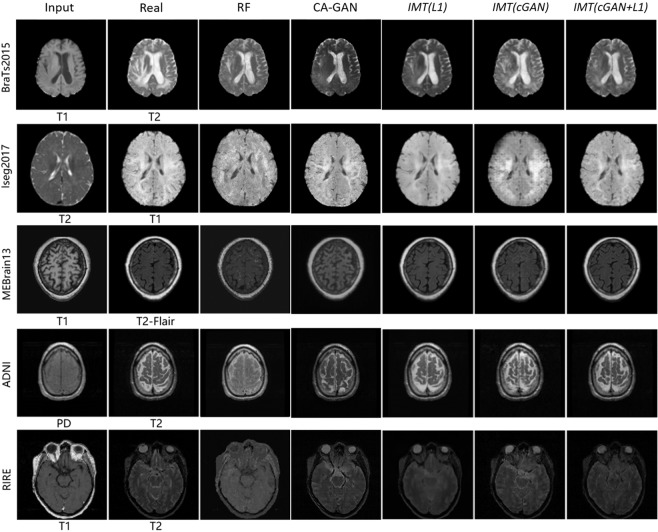

Figure 7 shows the qualitative results of cross-modality image generation using different approaches on five datasets. We have reasonable but blurry results using IMT network with L1 alone. The IMT network with cGAN alone leads to improvements in visual performance but causes some artifacts in cross-modality MR image generation. Using cGAN + L1 terms obtains sharp and realistic images and reduces artifacts. In contrast, the RF method and Context-Aware GAN lead to rough and fuzzy results compared with IMT networks.

Figure 7.

Samples of cross-modality generation results on five publicly available datasets including BraTs201560, Iseg201761, MRBrain1362, ADNI30, and RIRE63. Results are selected from top performing examples (relatively low MAE, high PSNR, high MI, and high PSNR collectively) with four approaches. The right five columns show results of the random-forests-based method (RF)5, the Context-Aware GAN (CA-GAN)30 and IMT framework with different loss functions (L1, cGAN, cGAN + L1).